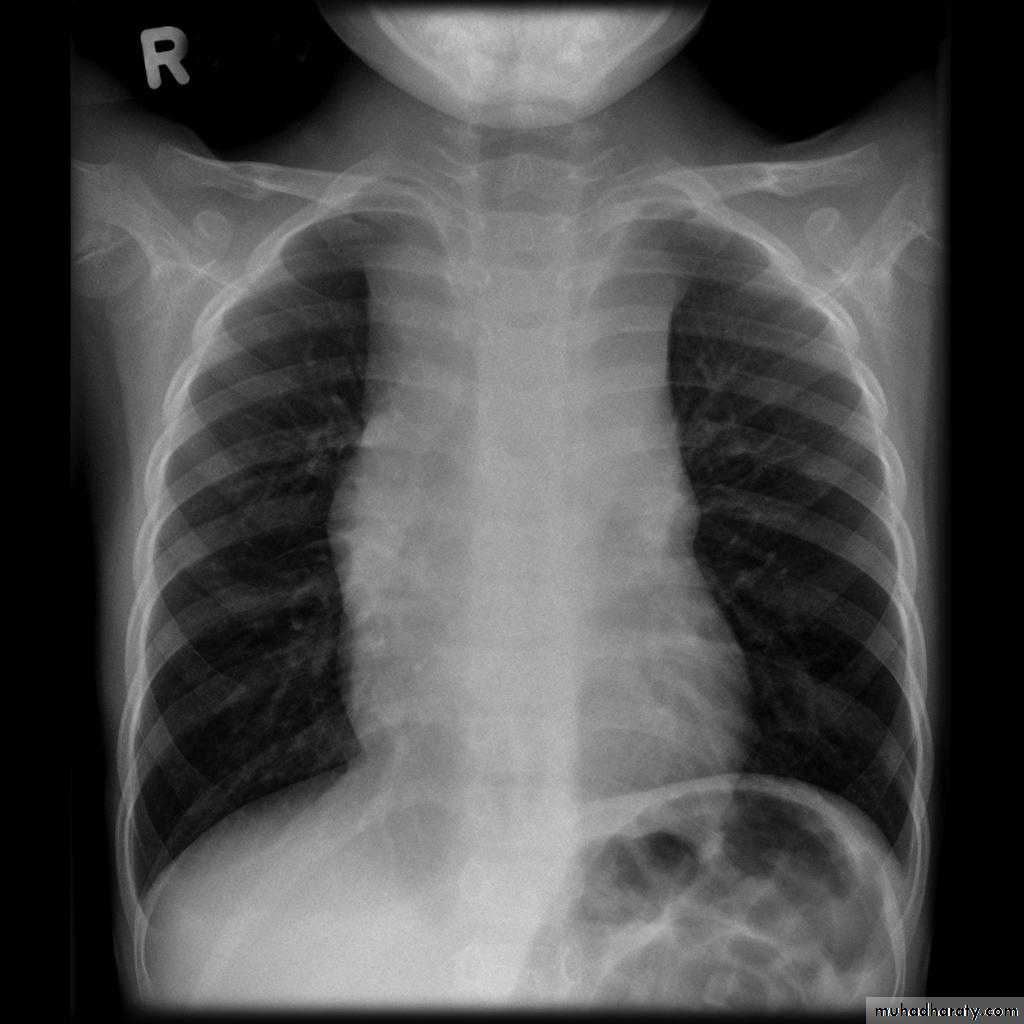

Normal thymus gland ( sail shape sign )